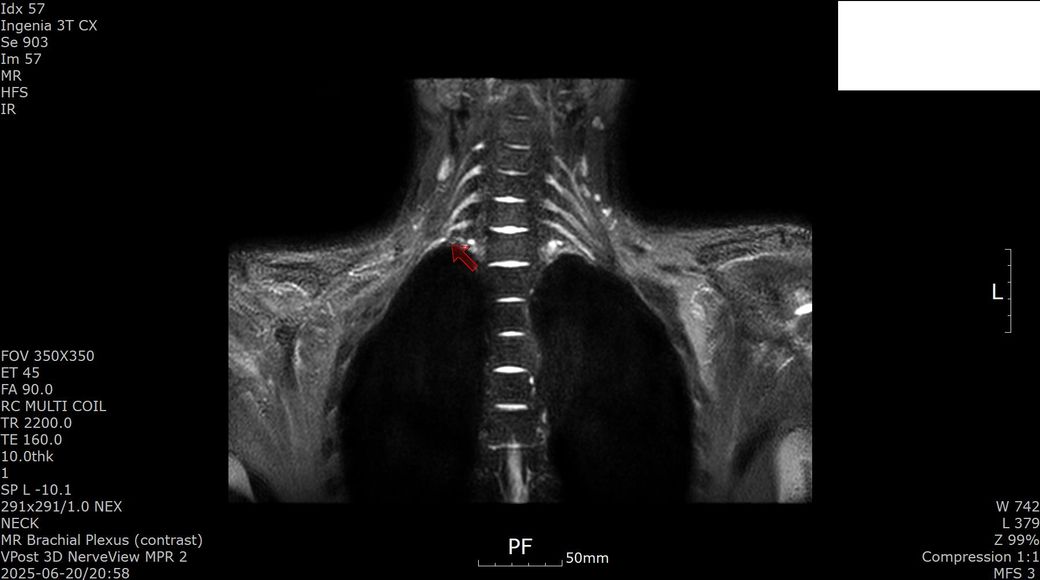

[상완신경총 brachial plexus] mri 판독 부탁드립니다

2025년 1월경 흉곽출구증후군(우측 사각근 유리술, 우측 제1늑골 제거술, 우측 상완신경총 박리술) 수술한 뒤 5개월 지난 2025년 6월경 상완신경총 mri 검사했습니다.

수술 후 발생한 증상과 mri 소견은 상완신경총 손상 또는 신경 재생 지연에 따른 합병증으로 보입니다.

이두근 위축과 근력 저하는 신경 기능 회복이 아직 진행 중임을 시사하고 감각 이상과 손가락 움직임 제한도 신경 손상의 영향일 수 있습니다. 치료는 신경재활치료, 물리치료, 근력 강화 운동과 함께 신경 재생을 돕는 약물치료가 필요하고 상태에 따라 추가 신경 수술이나 재활적 중재가 고려될 수 있습니다!